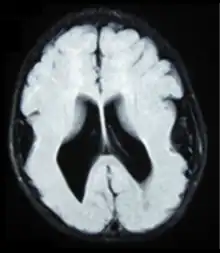

| Lissencephalic brain of a human, lacking surface convolutions (gyrification) | |

Lissencephaly (/ˌlɪs.ɛnˈsɛf.əl.i/, meaning 'smooth brain')[1] is a set of rare brain disorders whereby the whole or parts of the surface of the brain appear smooth.[2] It is caused by defective neuronal migration during the 12th to 24th weeks of gestation resulting in a lack of development of brain folds (gyri) and grooves (sulci).[3] It is a form of cephalic disorder. Terms such as agyria (no gyri) and pachygyria (broad gyri) are used to describe the appearance of the surface of the brain.